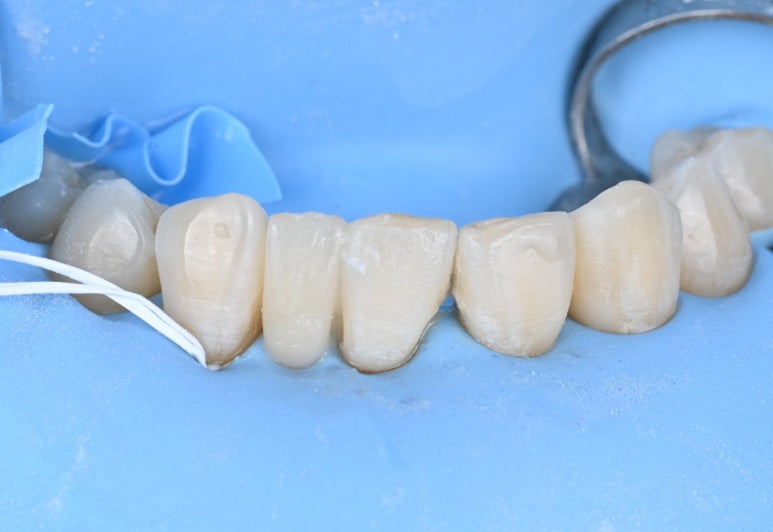

1) 러버댐 장착

레진 수복과 브릿지 접착 모든 과정에서

러버댐을 사용하여 입안의 습기를

완벽히 차단했습니다.

26.04.02 메릴랜드 브릿지 접착 준비